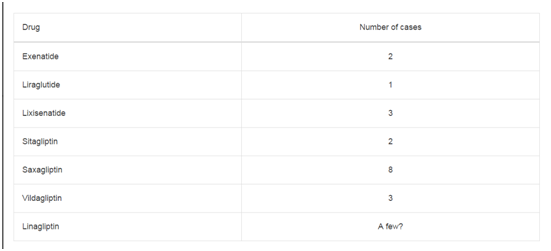

Table

Table: Table of the patients with lower extremity lymphedema.